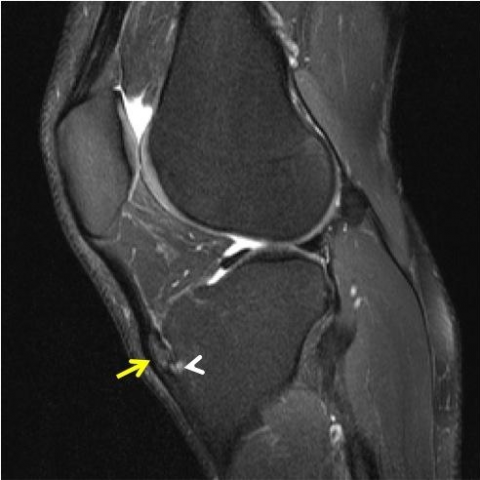

A história clínica e o exame físico, baseado na palpação local da proeminência óssea seguido por um raio-x é capaz de fechar o diagnóstico da doença. Alguns casos com recidivas ou sintomas mais graves a ressonância magnética pode ser solicitada para avaliar se durante o período de calcificação de uma das microfraturas não houve deslocamento de um fragmento.

(Imagem A) Demonstrando um raio-x normal. (Imagem B) Demonstrando a doença de osgood schlatter. (Imagem C) Ressonância magnética demonstrando a doença.